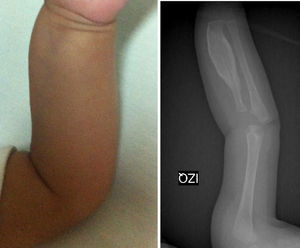

Los estudios de imágenes solicitados fueron radiografías simples de diferentes segmentos corporales, que demostraron una reacción perióstica (periostitis e hiperostosis) con cambios escleróticos, sin lesiones osteolíticas. Se apreció compromiso de la rama mandibular, el fémur izquierdo, la tibia y el radio bilateral. No se observaron microfracturas ni lesiones que involucraren metáfisis (figs. 1–4).

La enfermedad se caracteriza por neoformación perióstica y engrosamiento cortical que produce inflamación en el tejido muscular y conectivo circundantes. Se afecta la porción diafisiaria en los huesos tubulares y respeta la epífisis y la metáfisis. Puede afectar cualquier hueso, con excepción de las falanges, los cuerpos vertebrales y los huesos cuboideos12. No afecta la fisis de crecimiento13. Cuando la reacción subperióstica es muy importante entre huesos paralelos, se genera un aumento de presión y pérdida del tejido perióstico, con lo que puede ocurrir una fusión entre ambas corticales, descrito como puente interóseo. Esto puede resultar en secuelas y deformaciones óseas14; se han descrito casos de formas recurrentes15. Sin embargo, lo más frecuente es que la reacción perióstica se autolimite, se forme nuevo hueso subperióstico y el excedente de hueso periférico sea eliminado por remodelación16.

Los hallazgos radiológicos son la hiperostosis subperióstica cortical (engrosamiento perióstico) principalmente. Existe neoformación ósea subperióstica con incremento en densidad del grosor de la corteza17.